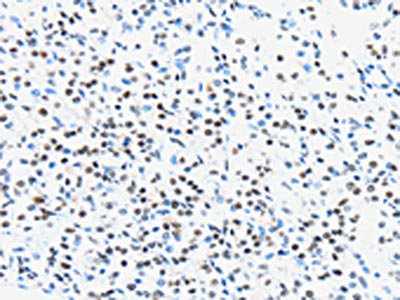

The image on the left is immunohistochemistry of paraffin-embedded Human breast cancer tissue using CSB-PA551947(UBA1 Antibody) at dilution 1/40, on the right is treated with synthetic peptide. (Original magnification: ×200)

The image on the left is immunohistochemistry of paraffin-embedded Human prostate cancer tissue using CSB-PA551947(UBA1 Antibody) at dilution 1/40, on the right is treated with synthetic peptide. (Original magnification: ×200)